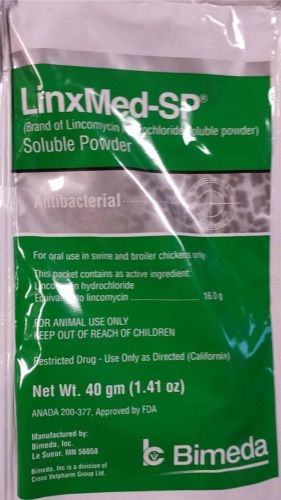

LinxMed-Sp Lincomycin hydrochloride Antibacterial Livestock soluble powder 40 Gr